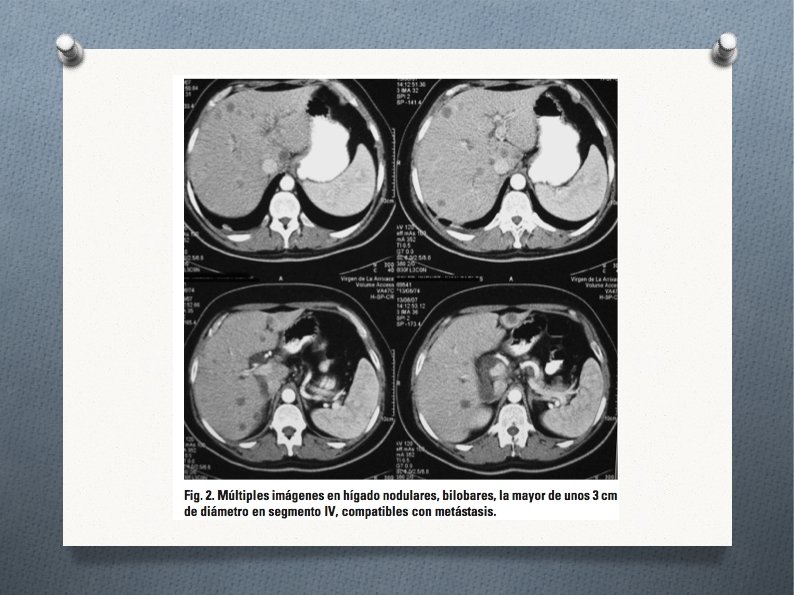

¿Qué PC solicitarías. . . ? ● ● TAC abdominal: múltiples imágenes en hígado, nodularesy bilobares, la mayor de unos 3 cm en segmento IV, compatibles con metástasis; masa situada a nivel inferior derecho de cabeza de páncreas, con necrosis central de aproximadamente 4 cm de diámetro, con importante compresión de duodeno, que provoca dilatación de la vía biliar en toda su extensión, así como del conducto pancreático; microadenopatías periféricas con vena y arteria mesentérica libres (figs. 1 y 2). Colangio-RM: masa en cabeza de páncreas; metástasis hepáticas.